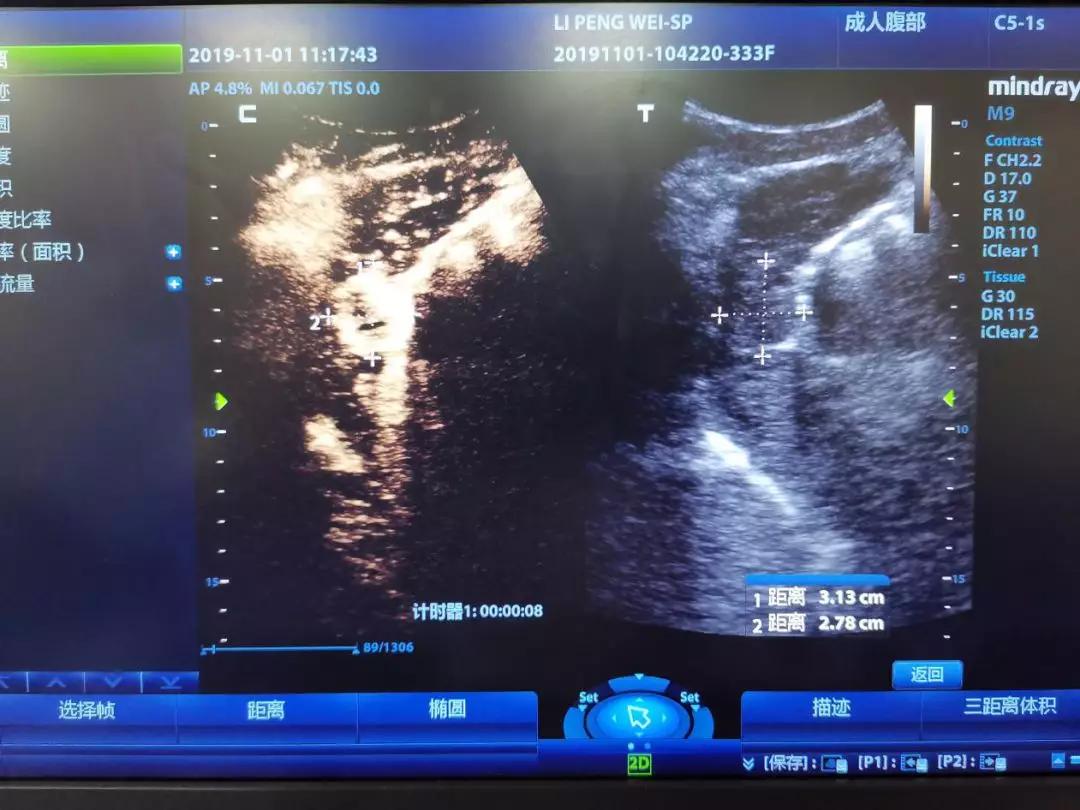

邻近胃肠的肝癌病灶,术前造影呈明显增强

超声造影是介入超声的一个好帮手,在整个手术的术前、术中、术后都需要用到超声造影。术前,主要是用来做评估是否需要做射频消融术及其范围。术中,超声造影可以引导射频消融术的位置。术后,主要是用于评估射频消融术的效果。多种超声技术的联合应用,可为肝癌精准的术前诊断、术中定位、术后评估起到重要作用。

邻近心包的肝癌病灶